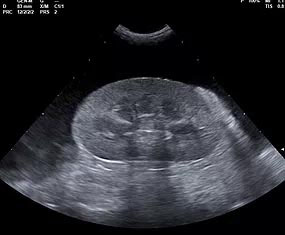

We elected to offer not only abdominal, cardiac and small parts ultrasound but also provide interventional procedures necessary to fulfill the diagnostic pathway. By doing so, we are capable of scanning a patient, working with attending veterinarians to assess patients for biopsy or aspiration and then collecting any samples that may be required to accurately diagnose and address the underlying concern.

At RVUS we have chosen industry leading equipment from vendors with reputable and proven track records in the industry. From the front lines to your final report it is imperative that the equipment and the user provide images that equip the specialists with the highest level of quality and reproducibility to confidently provide an accurate interpretation of the sonogram.

This, in turn, provides you with additional tools to arrive at a diagnosis and prognosis and to enhance the care model for your patient and confidence with your client. Our team of professionals with decades of ultrasound experience encourage the use of ultrasound as a leading route to non-invasively assess organs and pathology in question. To cover that spectrum, a variety of transducers are essential, all with different characteristics.

Whether your patient is 100 lbs or 10 lbs, take comfort in knowing your sonographer is capable of generating images that are sensitive and specific to the clinical concerns.